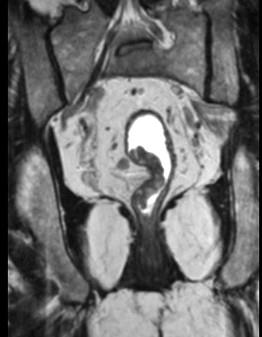

问题 男,70岁,下腹部腹胀、腹痛、排便困难,逐渐加重,MRI示直肠内不规则充盈缺损,请选择最佳诊断结果 ( )

选项 A、直肠转移瘤 B、直肠淋巴瘤 C、直肠癌 D、直肠间质瘤 E、直肠息肉

答案 C